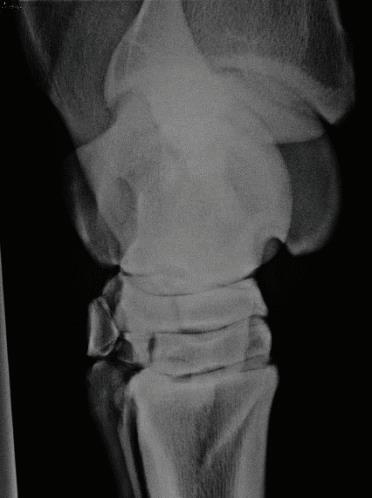

Fig 12: Purchase examination image on the left and lameness examination image on right 6 months post-purchase that blocked to an abaxial sesamoid block. Area of sclerosis and region of subchondral injury of the sagittal groove of the proximal first phalanx which may be enhanced by a slightly flatter beam angle.

Fig 12: Purchase examination image on the left and lameness examination image on the right 6 months post-purchase that blocked to an abaxial sesamoid block. Area of sclerosis and region of subchondral injury of the sagittal groove of the proximal first phalanx (P1) which may be enhanced by a slightly flatter beam angle.

Figure 12: Purchase examination image on the left and lameness examination image on the right six months post-purchase that blocked to an abaxial sesamoid block. Area of sclerosis and region of subchondral injury of the sagittal groove of the proximal first phalanx (P1) which may be enhanced by a slightly flatter beam angle.

Image courtesy of Dr. Richard D. Mitchell.